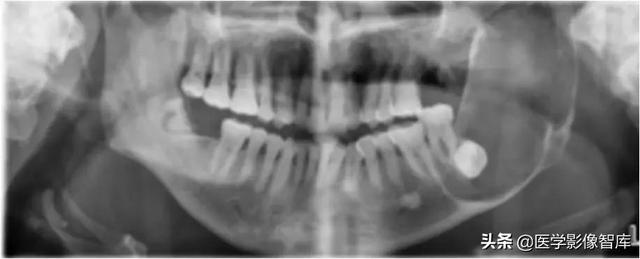

颌下间隙

64M,1个月前出现右下后牙钝痛伴咬合痛,自服红霉素,症状减轻。20天前发现患侧颌面及牙龈肿胀,伴有牙松动、牙周溢脓,抗炎效果不佳。约10天前曾行“脓肿切开引流”,#46、#47拔除。

骨髓炎并颌下间隙及下唇部感染。